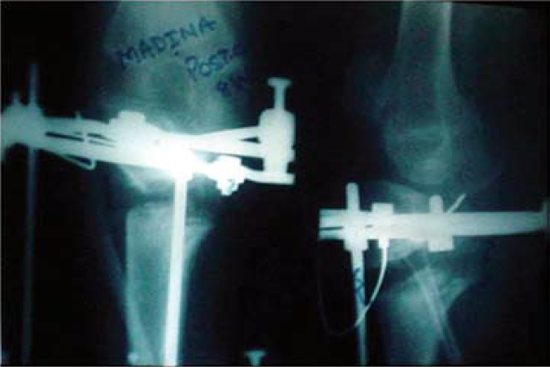

Knee Deformity